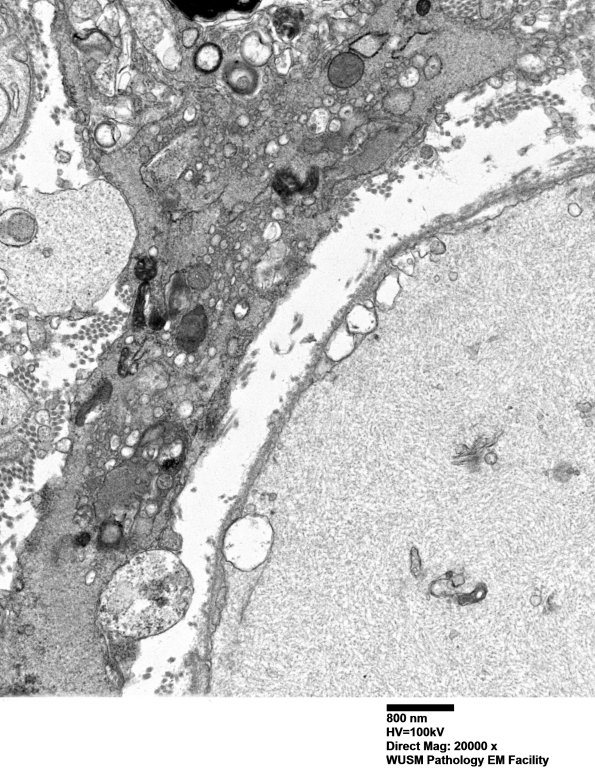

A macrophage with pseudopods surrounding a myelinated axon and adjacent to a large completely naked neurofilament containing axon. (electron micrographs)